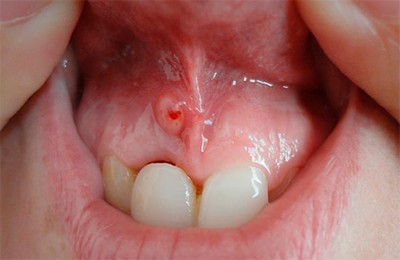

Пульпарный абсцесс

Скопление гноя в камере пульпы. После повышения в пульпе уровня серозного вещества происходит кислородная недостаточность.

Фото 1. Так выглядит осложнение пульпита, пульпарный абсцесс: на десне верхней челюсти заметно скопление гноя.

Нарушенный кислотно-щелочной баланс увеличивает количество молочной кислоты, что угнетает защитную клеточную функцию. Начинается распад тканей, и появляются симптомы абсцесса.